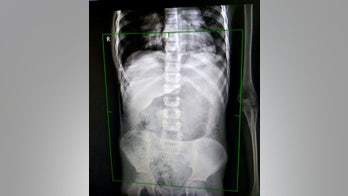

January 11, 2019 Mom recalls C-section horror when scar split days after birth A mom in Scotland said she remembers sitting on her couch thinking “Oh my god, I’m holding my intestines,” after her cesarean section scar split just days after her daughter’s 2011 birth.